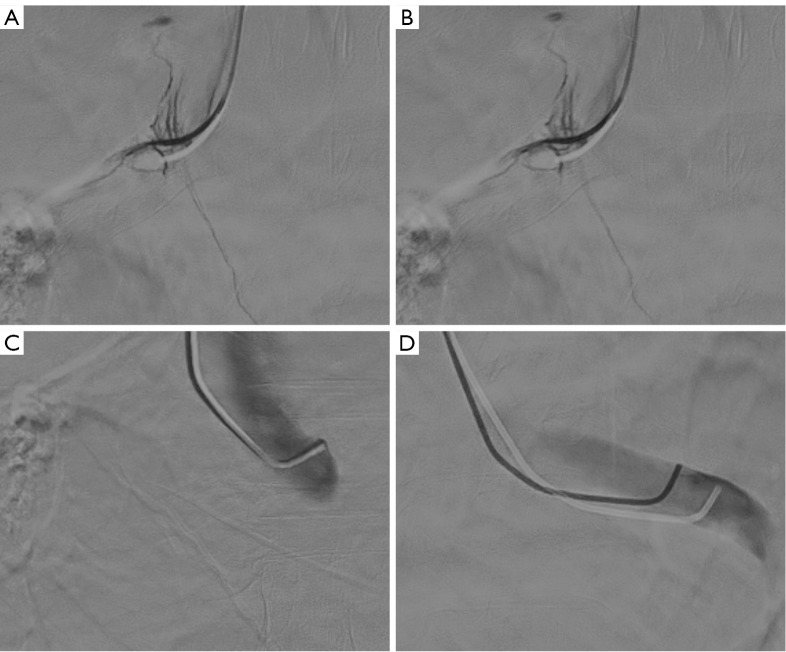

Background: Adrenal vein sampling (AVS) is the gold standard for diagnosing the dominant side in patients with primary aldosteronism (PA). CYP11B2 encodes aldosterone synthase. The aim of this study was to investigate the prognosis of dominant-side adrenalectomy in patients with PA identified by AVS in the context of aldosterone synthase expression in the postoperative pathology of those patients.

Methods: This retrospective study included 73 PA patients who underwent AVS followed by unilateral adrenalectomy. Patients were categorized into AVS bilateral success group, AVS unilateral success group, and AVS bilateral failure group based on their AVS status. Immunohistochemistry (IHC) for CYP11B2 was combined with postoperative pathology in these patients, and the clinical and biochemical prognosis of these patients was assessed 6 months after adrenalectomy.

Results: Between September 2023 and September 2024, 73 patients underwent unilateral adrenalectomy guided by AVS at our institution, with CYP11B2 IHC successfully performed in 63 cases. Among these, 21 patients (33.33%) achieved bilateral AVS success, 20 (31.75%) demonstrated unilateral AVS success, and 22 (34.92%) exhibited bilateral AVS failure. Pathological analysis of the bilateral AVS success group revealed aldosterone-producing adenoma (APA) in 12 cases, aldosterone-producing micronodule (APM) in 1, multiple-aldosterone-producing micronodules/nodules (MAPM/MAPN) in 2, aldosterone-producing diffuse hyperplasia (APDH) in 1, APA with MAPM in 3, and APA with APDH in 2. In this group, complete and partial clinical success rates were 47.62% (10/21) and 52.38% (11/21), respectively, while biochemical success rates reached 95.24% (20/21) for complete and 4.76% (1/21) for partial success. The unilateral AVS success cohort included APA (n=8), aldosterone-producing nodule (APN) (n=2), MAPM/MAPN (n=3), APA with MAPM (n=4), APA with APDH (n=2), and 1 CYP11B2 IHC-negative lesion, with clinical success rates of 40.00% (8/20) complete and 60.00% (12/20) partial, alongside 90.00% (18/20) complete and 10.00% (2/20) partial biochemical success. The bilateral AVS failure group comprised APA (n=8), MAPM/MAPN (n=1), APA with MAPM (n=5), APA with APDH (n=2), and 6 CYP11B2 IHC-negative lesions, demonstrating 36.36% (8/22) complete, 50.00% (11/22) partial, and 13.64% (3/22) no clinical success, with biochemical outcomes of 72.73% (16/22) complete, 18.18% (4/22) partial, and 9.09% (2/22) no success. Notably, bilateral AVS success correlated with significantly superior biochemical outcomes compared to bilateral failure (P=0.045).